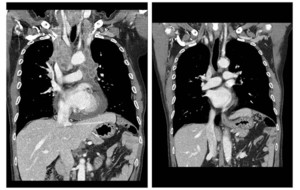

최근 2년간 내원한 복부대동맥류 파열 환자 생존률 높아스텐트그라프트 삽입술·하이브리드 수술 등 첨단기법 활용△일반 크기보다 1.5배 이상 증가복부대동맥류란 복부에 있는 대동맥이 혹처럼 늘어난 것을 말한다. 정상 복부대동맥의 직경은 2㎝ 내외인데, 일반적인 크기보다 1.5배 이상 증가하면 복부대동맥류로 진단한다. 복부대동맥류는 대부분이 특별한 증상이 없기 때문에 우연히 발견되는 경우가 많다. 문제는 증상이 없다가도 풍선처럼 늘어난 혈관이 갑자기 파열되는 경우 발생한다.대동맥이 파열되면 대량 출혈로 인해 환자의 절반 이상이 병원에 오지